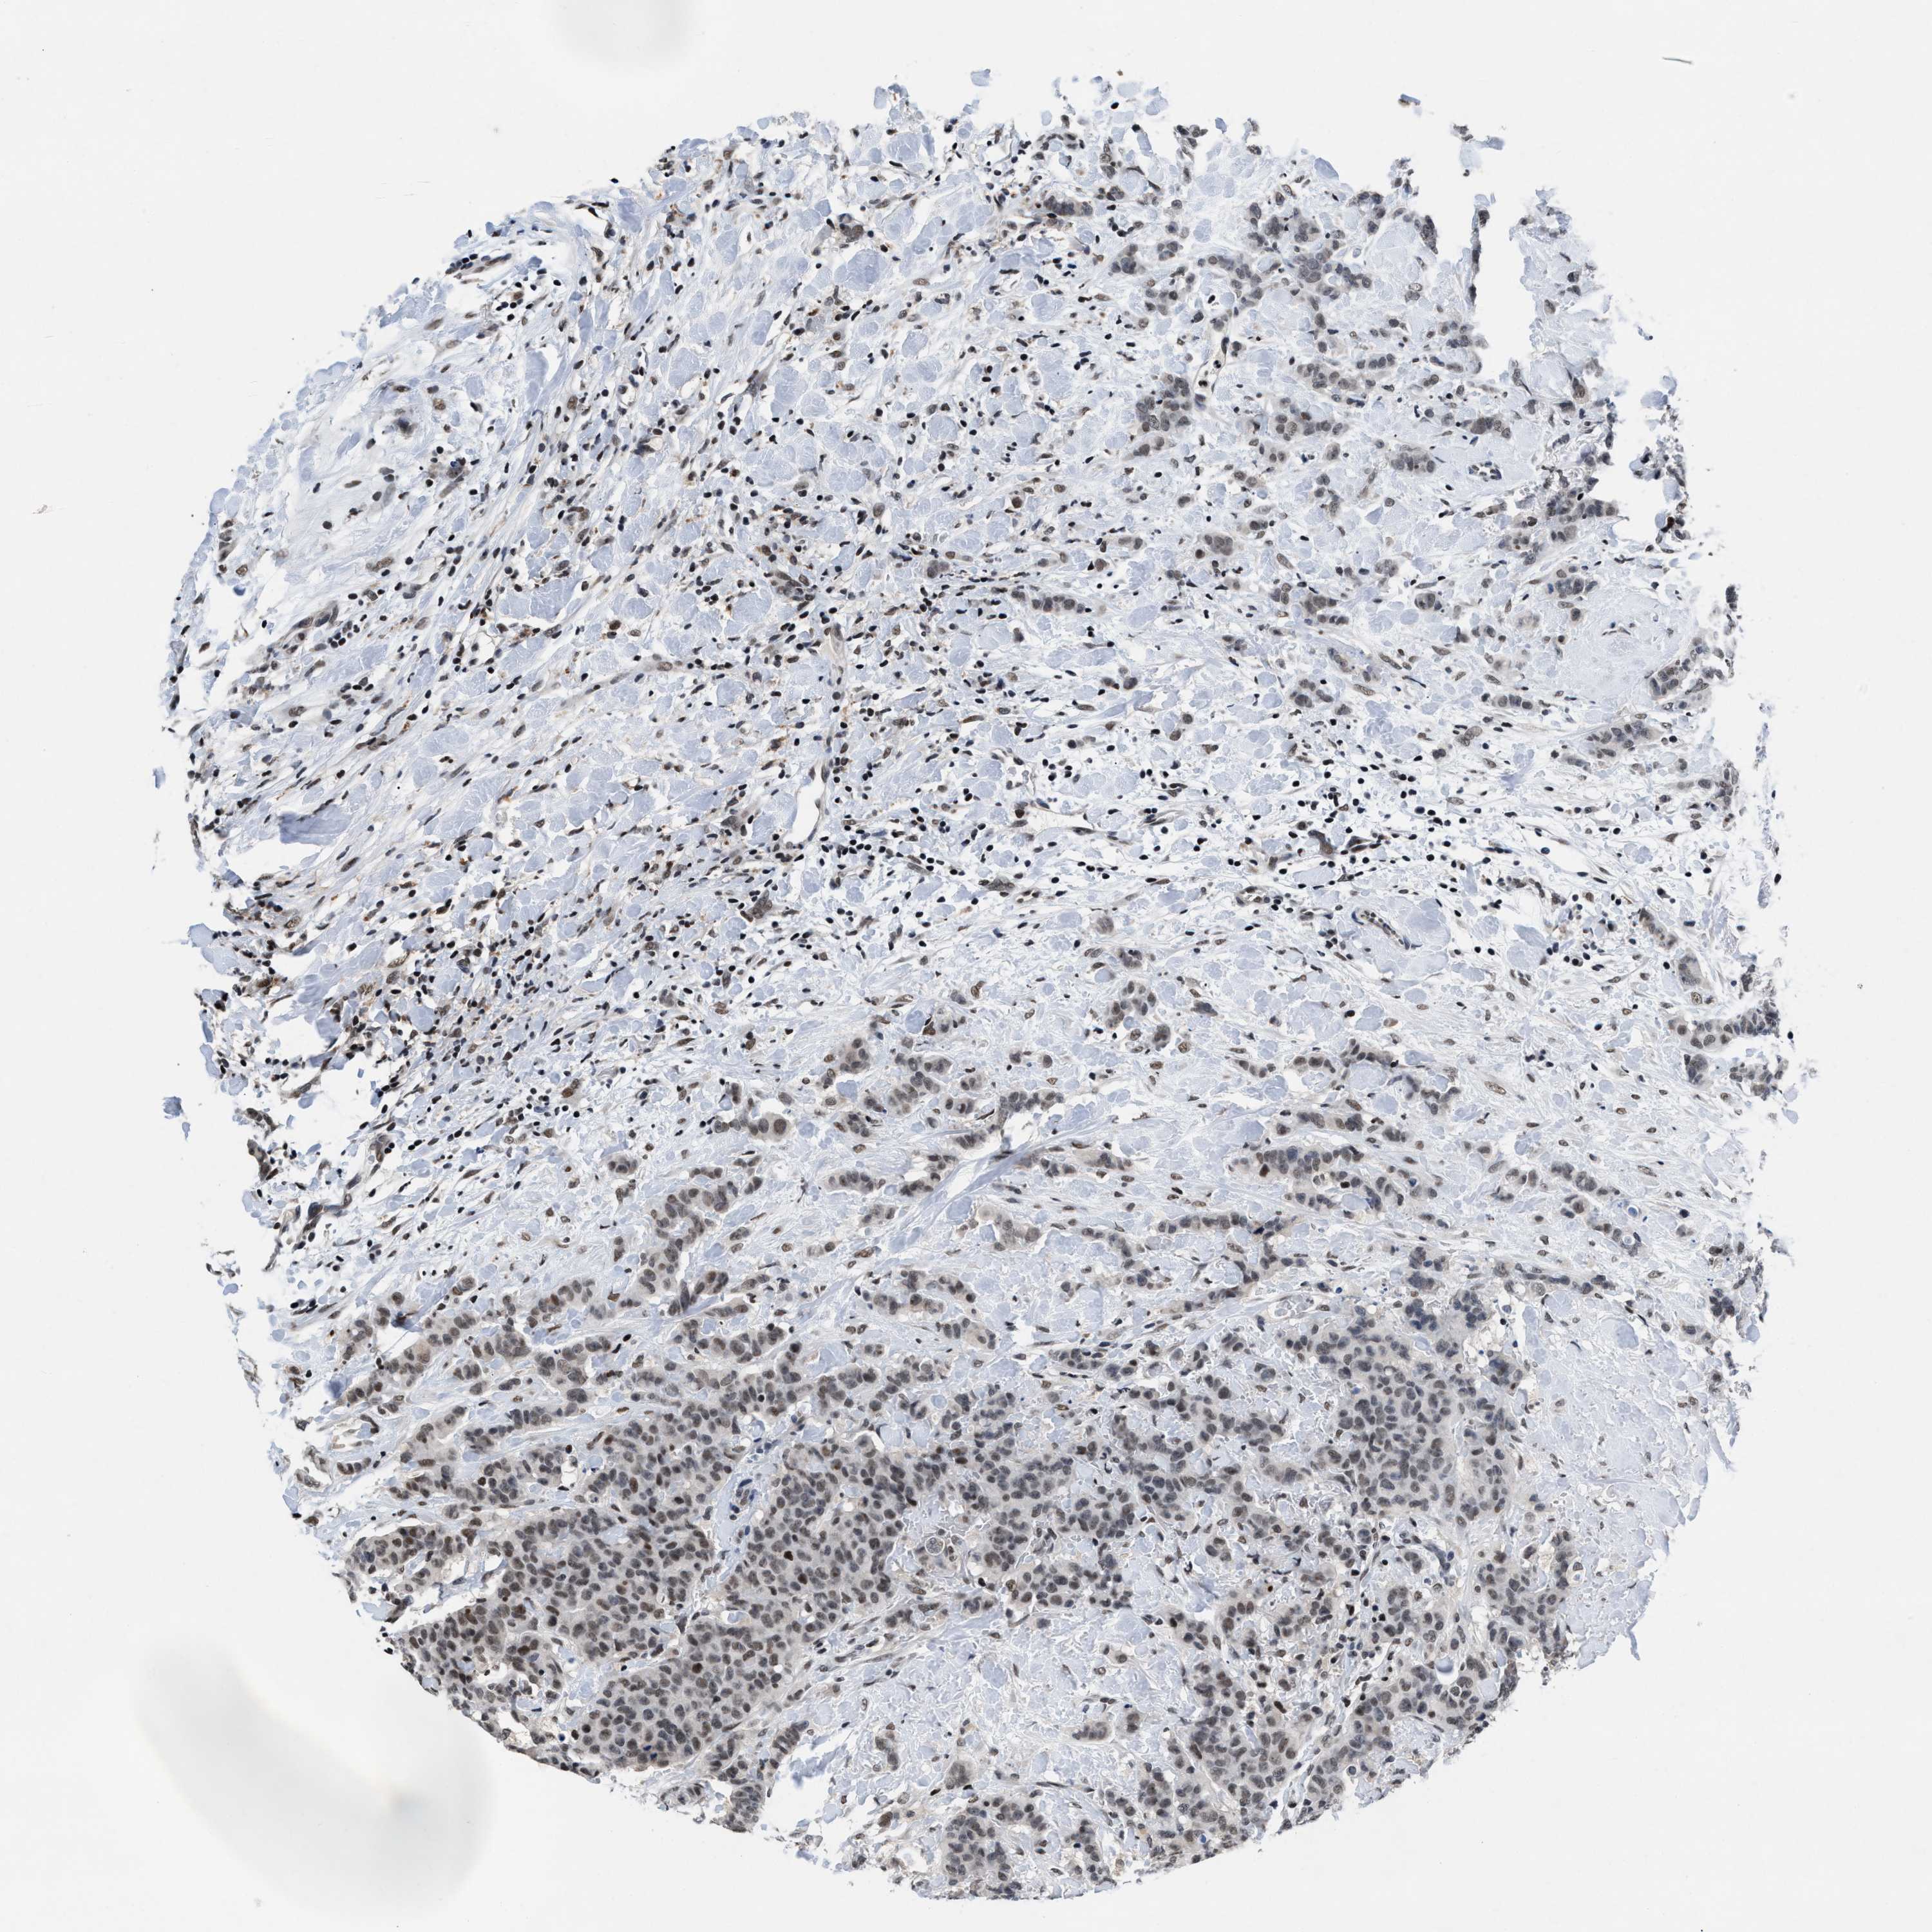

CANCER BREAST CANCER Show tissue menu

BRCA TCGA BRCA VALIDATION PROTEIN EXPRESSION

Breast cancer

Human cancer